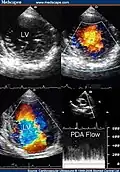

Two-dimensional apical four chamber and parasternal short axis images at the level of the ventricles show dilatation of both ventricles, multiple trabeculae and intertrabecular recesses in inferior, lateral, anterior walls, middle and apical portions of the septum and apex of the left ventricle. [1] -

Transthoracic two-dimensional study with color and continuous wave Doppler shows left ventricular noncompaction associated with patent ductus arteriosus (PDA). [2] -

Transthoracic two-dimensional echocardiogram in apical four chamber and parasternal short axis at the level of both ventricles demonstrate dilatation, deep trabeculae and intertrabecular recesses in the inferior, lateral, anterior walls, middle and apical portions of the septum and apex of the left ventricle. [3] -

Two-dimensional parasternal and color Doppler images at the level of both ventricles that show the noncompacted:compacted wall ratio and how the color enters the intertrabecular recesses [4]